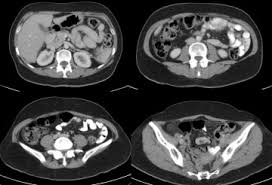

Malignant peritoneal mesothelioma (mpm) is an aggressive neoplasm that arises from the lining mesothelial cells of the peritoneum and spreads extensively within the confines of the abdominal cavity. Many of these signs and symptoms can be associated. Well differentiated papillary mesothelioma is characterized with a single layer of bland cuboidal cells lining fibrovascular cores, as demonstrated in this image. 13,28 malignant mesotheliomas of the peritoneum or pleura are rare tumors portending a poor prognosis. Home peritoneum peritoneum, omentum & mesentery mesothelioma. Additionally, omental mesothelioma is a rare type of mesothelioma that forms in the omentum, a part of the peritoneum that connects the stomach with other abdominal organs. Cystic epithelial neoplasms of the ovaries. A clinicopathologic study of 26 cases.

The tumor cells are strikingly similar to normal squamous. This type of cancer affects the lining that protects the contents of the abdomen and which also provides a lubricating fluid to enable the organs to move and. Cystic mesothelioma of the peritoneum. Approximately 35% of all mesotheliomas arise only from the peritoneum. A clinicopathologic study of 22 cases. Peritoneal mesothelioma is the name given to the cancer that attacks the lining of the abdomen. From there, they spread within the respective cavity and. Peritoneal mesothelioma is a cancer found in a thin membrane surrounding the abdomen known as the peritoneum. The majority of previously reported cases developed in the peritoneum of young women without a history of asbestos exposure. Adenocarcinoma) thus panel of immunohistochemical markers is generally required. A clinicopathologic study of 26 cases. Malignant peritoneal mesothelioma is the second most common form of mesothelioma and occurs in the tissue that lines the abdominal cavity and organs.1 the symptoms include pain and abdominal distention from ascites. Peritoneal mesothelioma affects the lining of the abdominal organs.

Malignant peritoneal mesothelioma is the second most common form of mesothelioma and occurs in the tissue that lines the abdominal cavity and organs.1 the symptoms include pain and abdominal distention from ascites.

The peritoneum is the serous membrane forming the lining of the abdominal cavity or coelom in amniotes and some invertebrates, such as annelids. Approximately 35% of all mesotheliomas arise only from the peritoneum. Please type a message to the paper's authors to explain your need for the paper. Peritoneal mesothelioma affects the lining of the abdominal organs. Malignant peritoneal mesothelioma is the second most common form of mesothelioma and occurs in the tissue that lines the abdominal cavity and organs.1 the symptoms include pain and abdominal distention from ascites.